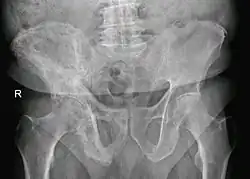

The exact cause is unknown, although leading theories indicate both genetic and acquired factors (see Causes). Paget's disease may affect any one or several bones of the body (most commonly pelvis, tibia, femur, lumbar vertebrae, and skull), but never the entire skeleton,[1][2][3] and does not spread from bone to bone.[4] Rarely, a bone affected by Paget's disease can transform into a malignant bone cancer.

- Pagetic bone has a characteristic appearance on X-rays. A skeletal survey is therefore indicated.

- Bone scans are useful in determining the extent and activity of the condition. If a bone scan suggests Paget's disease, the affected bone(s) should be X-rayed to confirm the diagnosis.